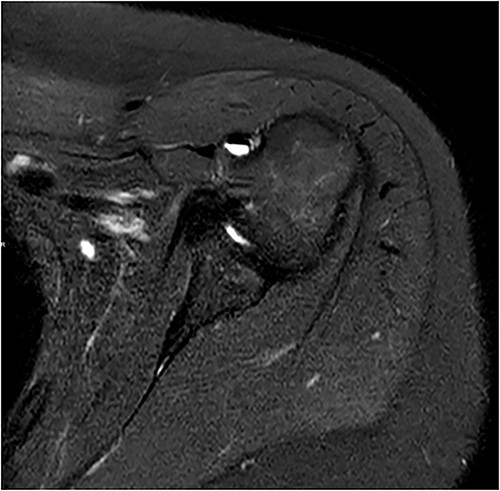

Coronal and axial T2 fat saturated image of left shoulder showing thickened inferior capsule of low T2 signal, characteristic of freezing phase in adhesive capsulitis.

Coronal and axial T2 fat saturated image of left shoulder showing thickened inferior capsule of low T2 signal, characteristic of the freezing phase in adhesive capsulitis.